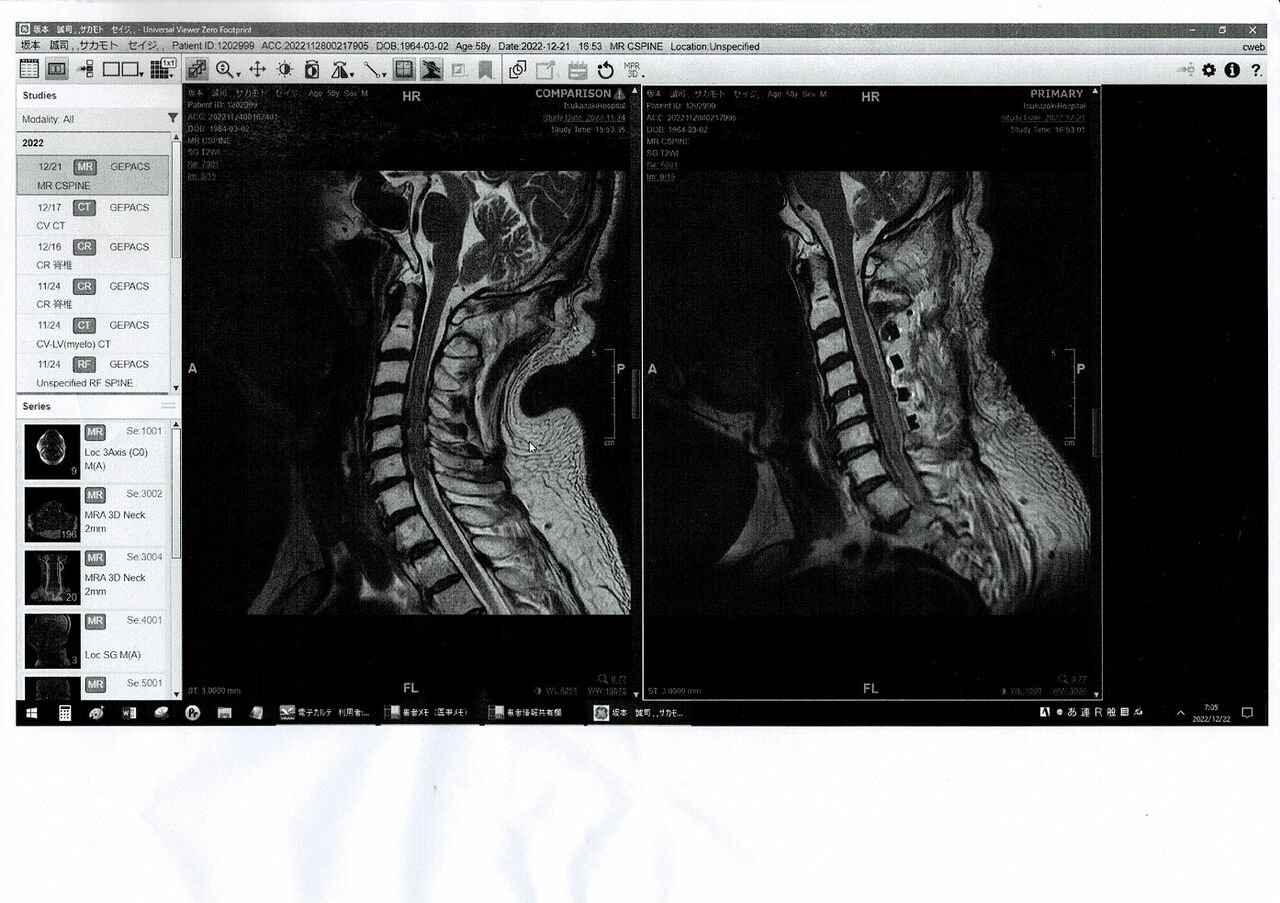

´âŦ½Ð¤«¤é2ǯ°Ê¾å·Ð²á¤·¡¢ÀèÆü¤ÎCT¸¡ºº¤Î·ë²Ì¤Ç¤¹¤¬¡Ä

´â¤Îž°Ü¡¢ºÆÈ¯¤¬Ìµ¤¤¤«¤È¸À¤¦»ö¤Ç¡¢¾åȾ¿È¤òCT¥¹¥¥ã¥ó¤·¤¿½ê

¹¬¤¤¤Ê»ö¤Ë¡¢Å¾°Ü¡¢ºÆÈ¯¤ÎÃû¸õ¤Ï³Îǧ½ÐÍè¤Ê¤«¤Ã¤¿¤Î¤Ç¤¹¤¬

¼Â¤Ï¿ô½½Ç¯Á°¤«¤éʬ¤«¤Ã¤Æ¤¤¤¿»ö¤Ç¡¢ËͤΤ¹¤¤Â¡¤Ë¤ÏÌäÂ꤬¤¢¤ê

º£²ó¤â¤½¤ÎÉôʬ¤ËÉÕ¤¤¤Æ¡¢¼ç¼£°å¤«¤é¿§¡¹¤È¤ªÏ䬤¢¤ê¤Þ¤·¤¿¡£

²áµî4²ó¤Û¤ÉÃÀÆ»Êĺɤǻà¤Ë³Ý¤±¤¿»ö¤¬¤¢¤ë¤Î¤Ç¤¹¤¬

°ì½ï¤ËCT²èÁü¤Î¿ÇÃǤòʹ¤¤¤Æ¤¤¤¿²Ç¤ÏȾ¾Ð¤¤¤Ç

²Ç¡Öº£ÅÙ¤Ïç¹Â¡¤Î¼ê½Ñ¤ä¤Ê£÷¡×¤È¤Û¤¯¤½¾Ð¤ó¤Ç¤¤¤Þ¤·¤¿¡Ä¡£

¼è¤ê¹ç¤¨¤º¼ó¤Î¼ê½Ñ¤ò¤·¤¿¤Ð¤«¤ê¤Ê¤Î¤Ç

¤É¤¦¤¹¤ë¤«¤Ï©»Ò¤ÈÁêÃ̤·¤Ê¤¬¤é»Ã¤¯Çº¤à»ö¤Ë¤·¤Þ¤¹¡Ä¡£